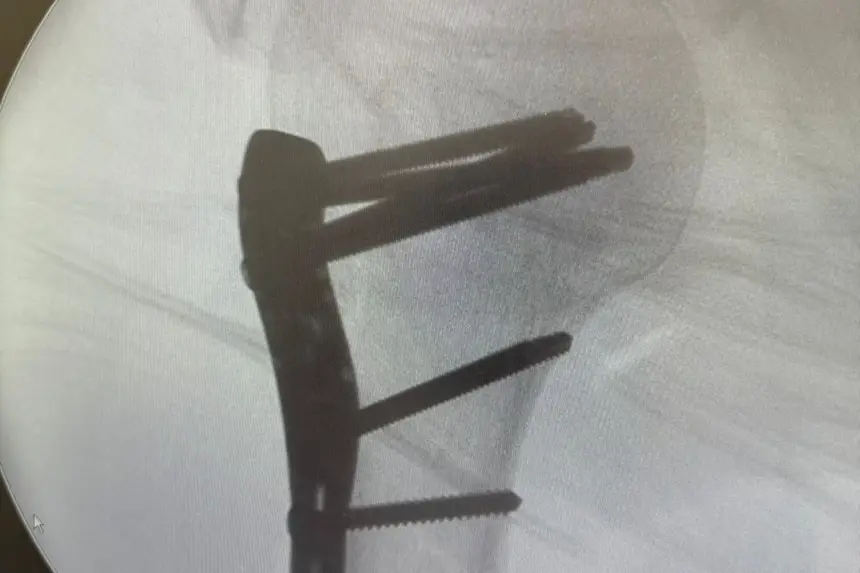

CIRURGIAS ORTOPÉDICAS

Sesa deu total suporte para o aumento da demanda de cirurgias ortopédicas

Entre os dias 23 de dezembro e 1º de janeiro, 109 pacientes vítimas de acidentes automobilísticos deram entrada no Hospital de Emergências (HE). Em um único dia, mais de 20 pessoas foram atendidas em decorrência desse tipo de ocorrência. Esse cenário resultou em um aumento significativo na demanda por cirurgias ortopédicas, principalmente em função de fraturas e traumas graves.

A maioria dos pacientes chegou à unidade com fraturas expostas, lesões em membros superiores e inferiores e traumas múltiplos, muitos deles causados por colisões envolvendo motocicletas. O fluxo intenso impactou diretamente a rotina do hospital, ocasionando corredores com pacientes aguardando entrada para cirurgia, enquanto equipes médicas e assistenciais atuavam de forma contínua para garantir um atendimento rápido e seguro.